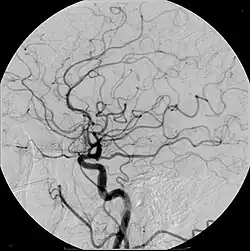

Cerebraal angiogram met afgebeeld onder andere de cirkel van Willis

Digitale subtractieangiografie of DSA is een angiografische techniek die wordt gebruikt in de interventieradiologie. Met deze techniek worden duidelijke afbeeldingen van bloedvaten gemaakt in een omgeving met veel botstructuren of andere weefsels met een hoge dichtheid. De gemaakte afbeelding wordt een angiogram genoemd. De afbeeldingen worden gemaakt door gebruik te maken van contrastmiddel, waar meestal jodium aan is toegevoegd. Eerst wordt voor toediening van dit middel een precontrast röntgenfoto gemaakt. Hierna wordt het contrastmiddel toegediend en opnieuw een foto gemaakt. Door vervolgens beide afbeeldingen van elkaar af te trekken, blijft alleen het verschil tussen beide afbeeldingen, namelijk de structuur van de bloedvaten met het contrastmiddel over.